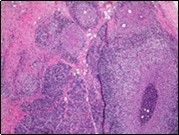

Core needle biopsy of idiopathic granulomatous mastitis enunciates multiple aggregates of non- caseating epitheloid cell granulomas within and encompassing breast lobules, constituted of epitheloid histiocytes, lymphocytes, neutrophils and multinucleated giant cells. Granulomatous inflammation is predominantly lobulo-centric. The inflammation is preponderantly composed of lymphocytes, plasma cells, epitheloid histiocytes, multinucleated giant cells and neutrophils. Neutrophils can configure micro-abscesses and encompass vacant micro-cystic cavities, morphological features which are in common with cystic neutrophilic granulomatous mastitis. Non specific lobulitis along with a lymphoid and plasma cell infiltrate accompanies the granulomatous inflammation. Necrosis is usually absent. Neutrophilic micro-abscesses can be accompanied by fistula formation 4, 5.

Multinucleated giant cells are detected in an estimated three fourths (78.5%) instances. Plasma cells are discernible in around half (53.9%) of the subjects and usually appear at the margins of cystic vacuoles with centric accumulation of neutrophils within the granulomas.

Figure 1.Granulomatous mastitis with the configuration of epitheloid cell granuloma and a lymphoid and plasma cell infiltrate9.

Figure 2.Granulomatous mastitis with articulated epitheloid cell granuloma, lymphocytic, plasma cell and neutrophilic infiltration10.

Figure 3.Granulomatous mastitis with scattered langhans and foreign body giant cells, epitheloid cell granuloma and lymphoid ingress11.

Figure 4.Granulomatous mastitis with epitheloid cell granuloma, langhans and foreign body giant cells with lymphocytic rimming12.